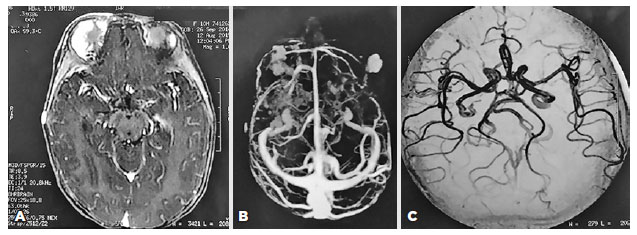

Considering those clinical findings, a diagnosis of PHACE syndrome was made (hemangioma greater than 5 cm plus MGDA). In this way, screening to detect other malformations was performed. Magnetic resonance angiography of the brain and face showed multiple areas of pathological contrast enhancement suggestive of superficial frontotemporal hemangiomas on the right side and a malar on the left side, but cerebral vascular disorders and malformations were not observed (Figure 3). No abnormalities were seen on echocardiogram, abdominal Doppler ultrasound, or electroencephalography. The systemic clinical assessment was normal, except for a glottic hemangioma in the otolaryngologic examination.